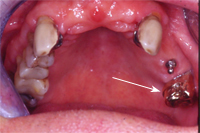

Dieser 67 Jahre alte Patient trägt seit knapp dreissig Jahren im Oberkiefer eine Teilprothese, an die er sich restlos gewöhnt hat und die er eigentlich noch lange behalten möchte (Abb. 7).

Die Situation ist jetzt aber ungünstig geworden, da der alleinstehende Backenzahn auf der einen Seite stark wackelt (Abb. 8, weisser Pfeil). Dieser hat in den 30 Jahren einen viel grösseren parodontalen Schaden erlitten, als die gesamte Gruppe der eigenen Zähne auf der Gegenseite, die keine Parodontitis aufweisen.

Zur Unterstützung haben wir also auf der schwachen Seite ein Implantat mit Sinuslift gesetzt, welches wir viereinhalb Monate später mit einem Druckknopf versehen haben (Abb. 8 und 9). In die Teilprothese wurde als Gegenstück eine Druckknopfhülse eingebaut (Abb. 10).